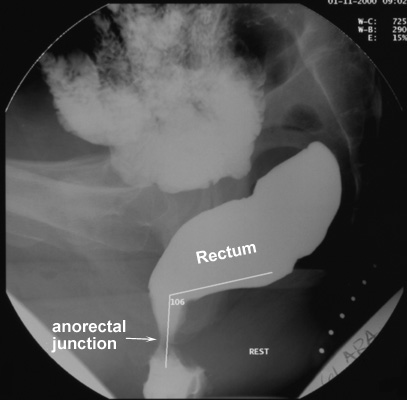

Anorectal junction position

- The site of the anorectal junction is the point where

the parallel straight sides of the anal canal convert to the diverging

walls of the distal rectum.

- This point is measured with reference to the

inferior margins of the ischial tuberosities.

- In young subjects, the anorectal junction lies close to this bony landmark.

- During maximal

straining, the anorectal junction should descend a distance of no more

than 3.5 cm from its resting position.